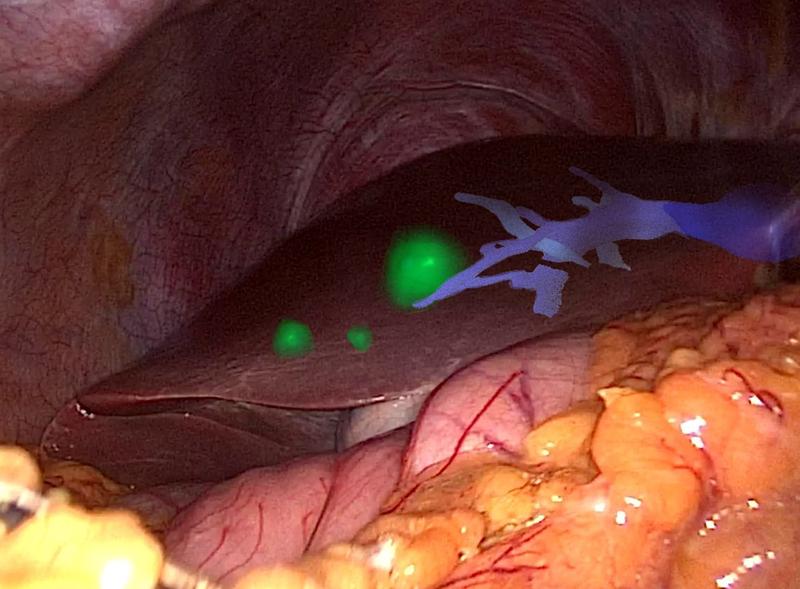

Informatikerin entwickelt Assistenzsysteme für die Krebschirurgie

Adresse eingeben, okay drücken, losfahren. Im Auto verlassen wir uns ganz selbstverständlich auf unser Navigationssystem, wenn wir zu neuen Zielen aufbrechen….